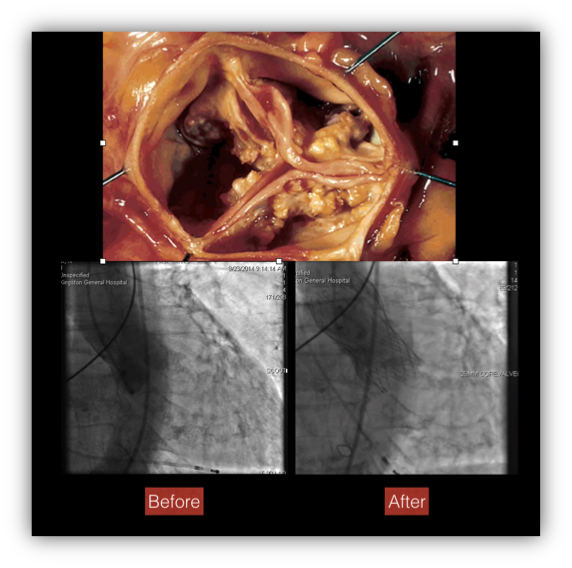

She continues to have syncope despite the pacemaker and you determine it is due to her critical aortic stenosis. You refer her for transcatheter aortic valve implantation (TAVI). She undergoes successful placement of a #26 Medtronic CorValve

The patient had degenerative, calcific aortic stenosis

TAVI has proven to be the equal of conventional aortic surgery.

In 1966 most centres did not offer aortic valve surgery, and those that did usually restricted its application to patients under 65 years of age. Our patient would likely have died within 1-2 years due to critical aortic stenosis with little cost to the system.